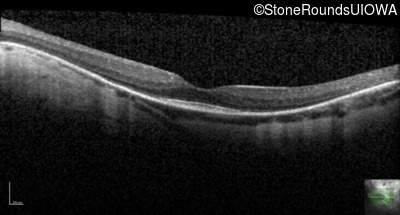

Optical Coherence Tomography - Left - 20/25 -1

Exemplar / OCT Stack

OCT Stack